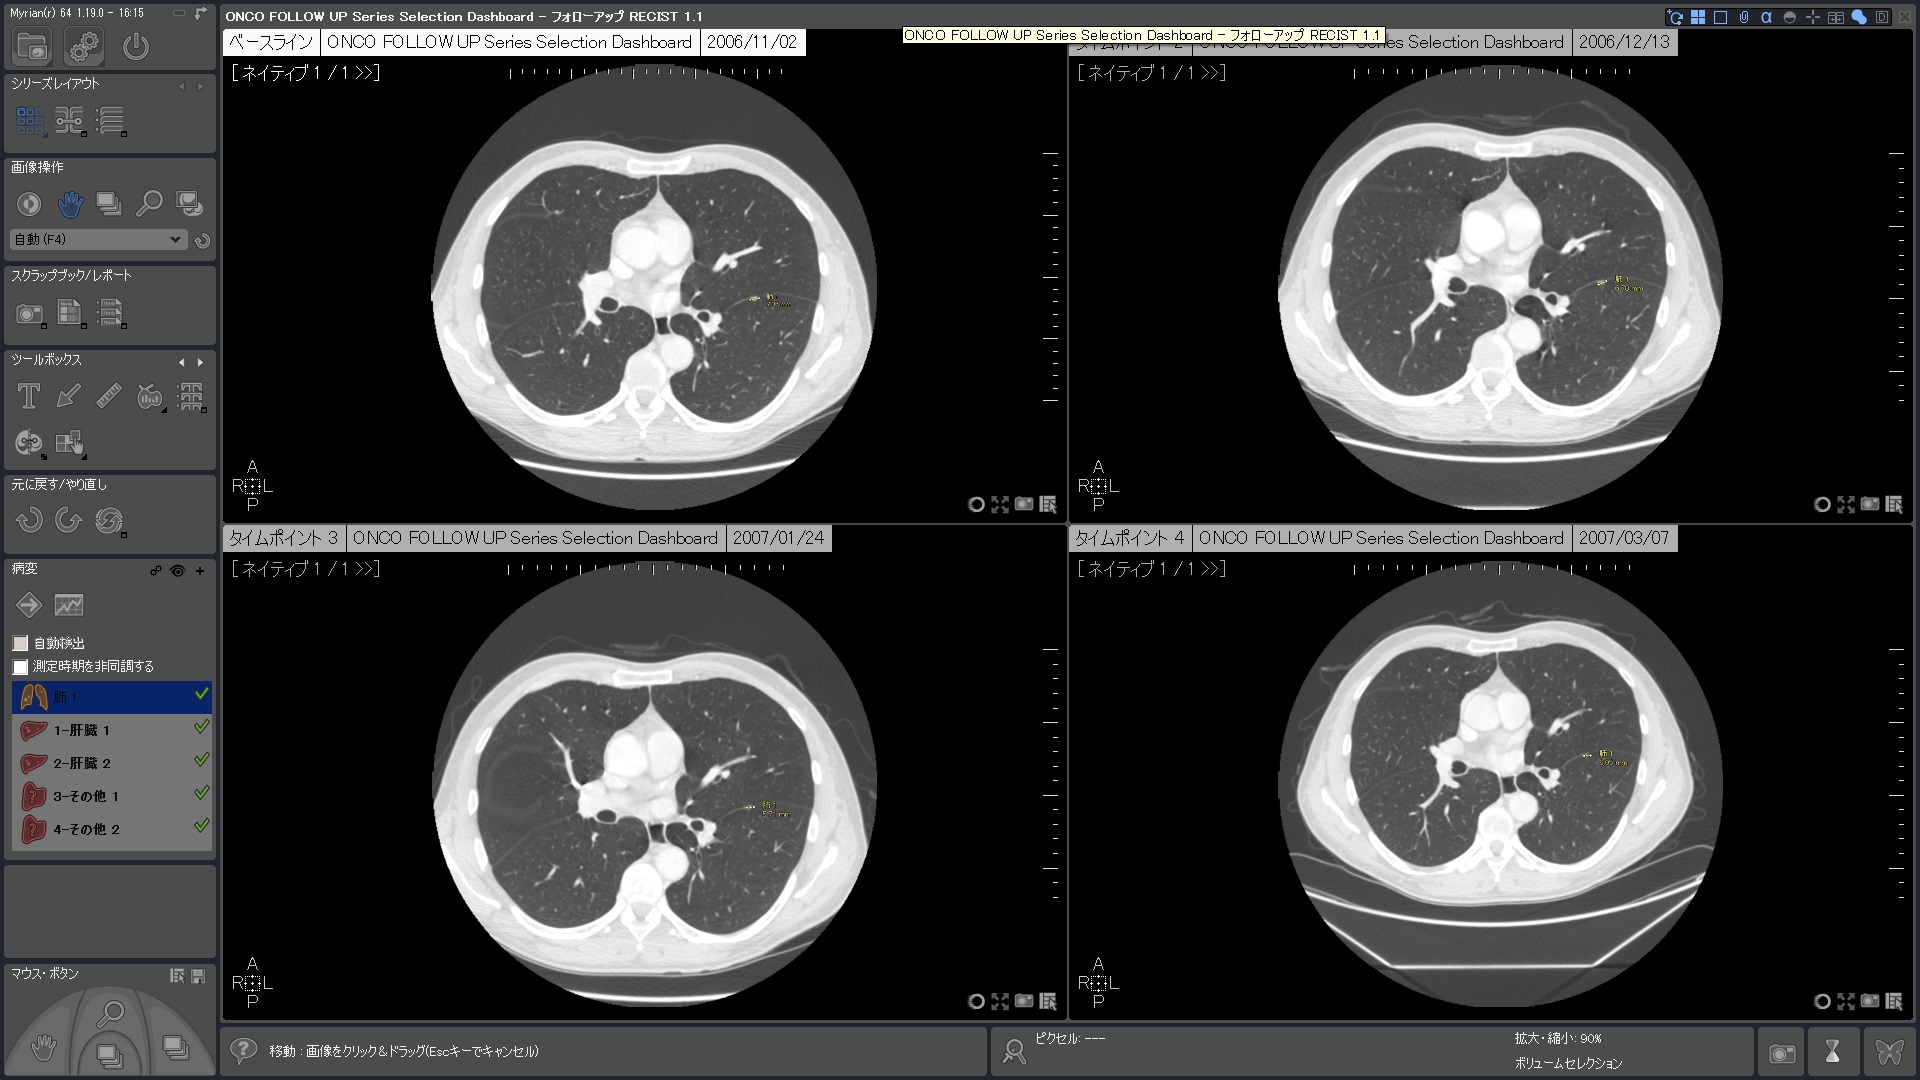

| 3.次のタイムポイントでは自動でロードされ、正確に位置合わせたROIを 素早く計測 |

フォローアップに必要なすべてのステップは自動化されています。 ベースライン作成後、次のタイムポイントでは自動的に非剛体レジストレーションが行われ、高速な検査比較が可能です。必要に応じて自動で国際評価基準(RECIST1.0,1.1)に沿った治療レスポンスが計算され、PACSへ転送されます。そし検査レポートも自動作成されます。